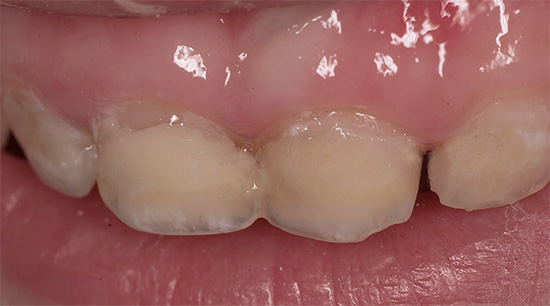

La seguente foto mostra un tipico esempio di carie di bottiglie:

Per analogia, la carie in bottiglia è anche chiamata "vivaio", "kefir", "latte", ci sono persino i nomi "carie al capezzolo" e "carie per l'alimentazione notturna" - questi termini indicano chiaramente anche le principali fonti del problema e l'età dei pazienti. Nelle directory mediche, tutti questi termini non esistono affatto: per natura del corso e cause primarie, la malattia è tipica carie e il nome "carie in bottiglia" è comune.